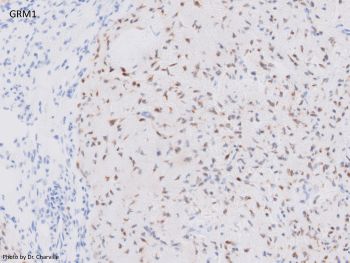

Chondromyxoid fibroma is a benign neoplasm that commonly involves the craniofacial (jaw and sinonasal) bones. Histologically, it is comprised of lobules of spindled and stellate cells with chondromyxoid background, arranged in a zonal architecture (i.e. hypercellular periphery and hypocellular center). Coarse calcifications can be seen. GRM1 expression by immunohistochemistry is a good surrogate marker for GRM1 gene recombination which is present in the majority of CMF cases.